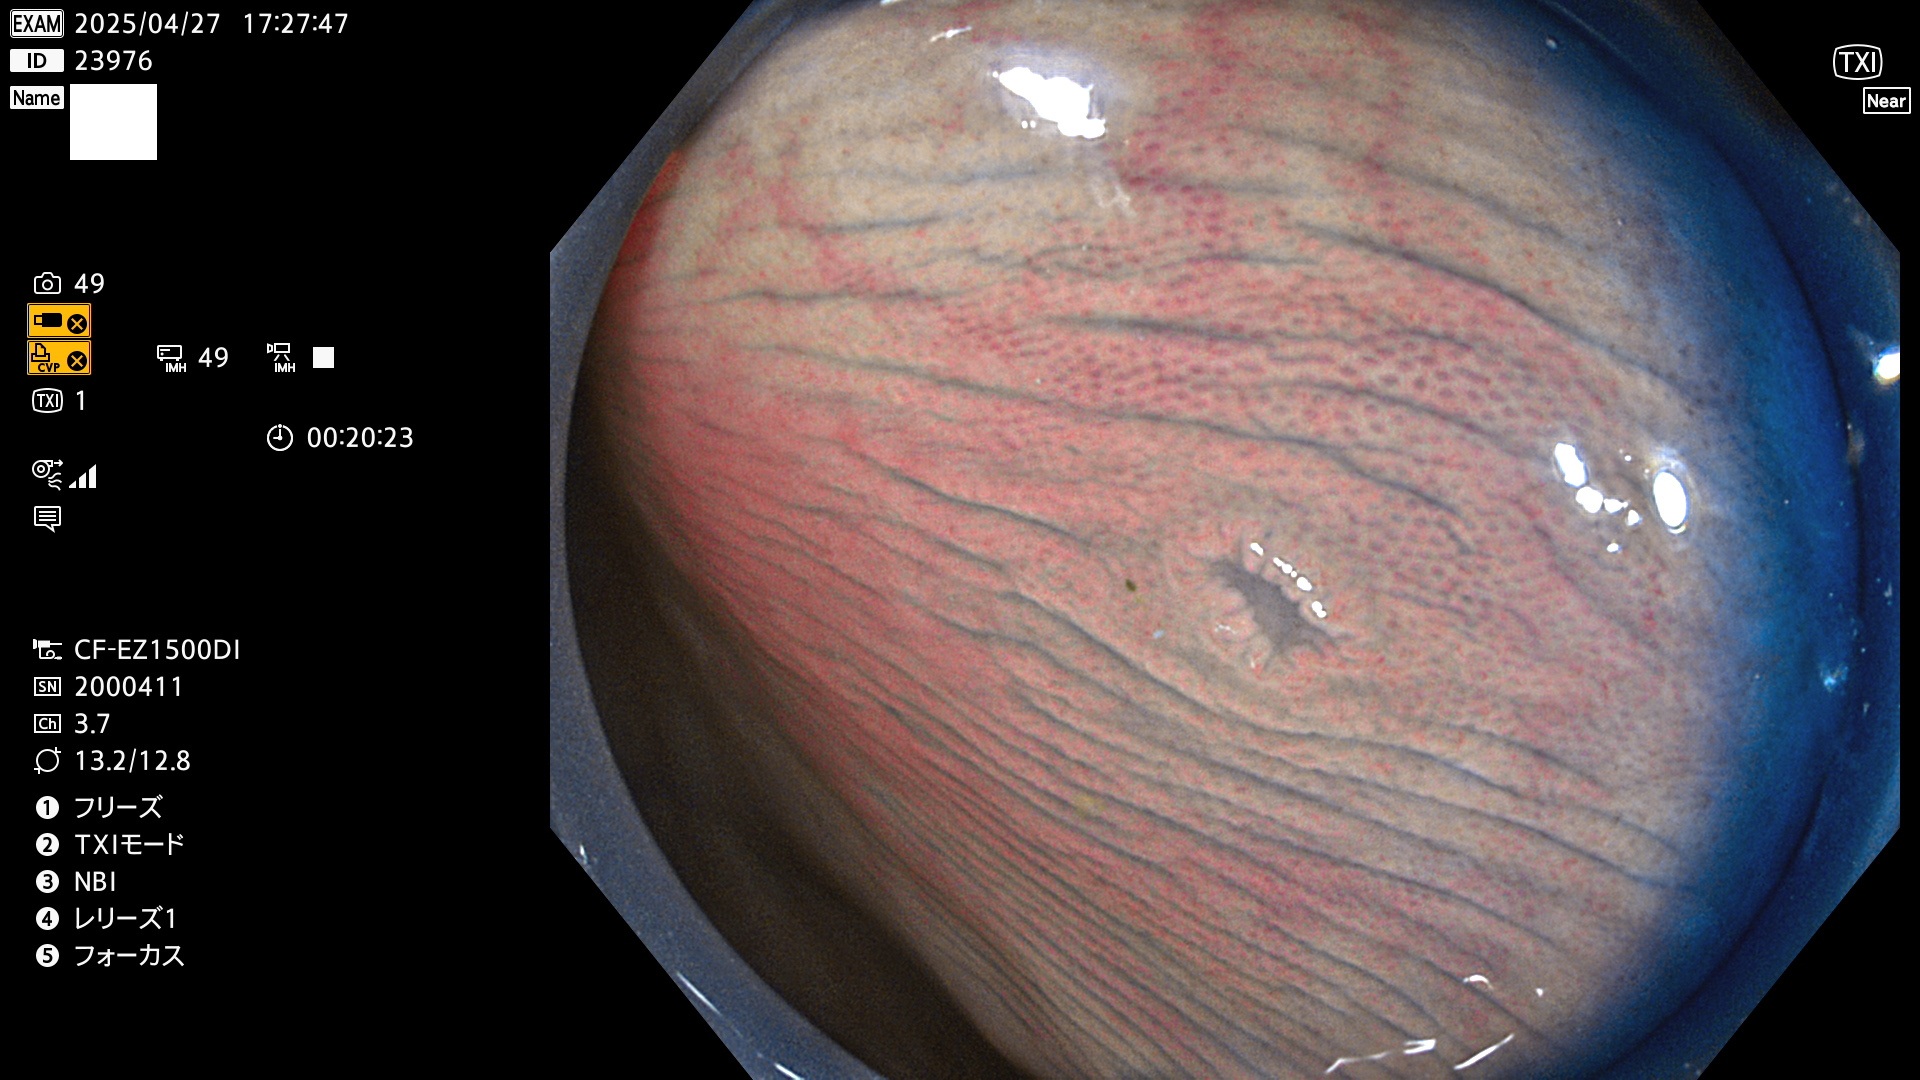

完全に平坦な物をUb、陥凹している物をUcと呼びます。Ubは認識が困難で、Ucはびらん(炎症)と紛らわしいために見落とされやすく、「内視鏡後・大腸癌」の原因になります。

抽出の対象期間 2025年4月24日〜4月27日の4日間(48件の検査)4個 (4/48=8%)